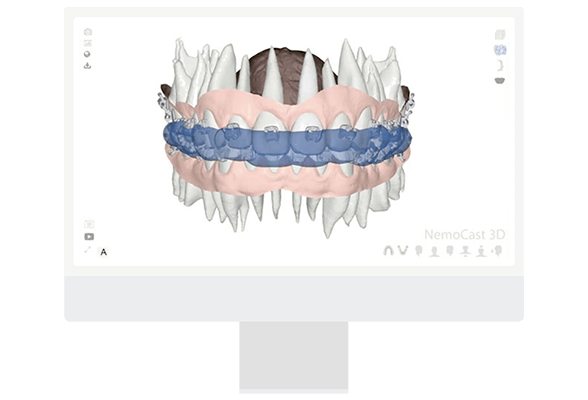

Image (A): Noise removal and alignment of the intraoral scan in NemoCast.

Image (B): Final clean digital model ready for orthodontic planning.

- Dynamic analysis of occlusion

Dynamic analysis of occlusion using the virtual articulator. Display of distances and occlusal contacts through a virtual simulation. Possibility for individualization and personalized adjustment. Imports dynamic maxillofacial relations.